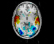

Objects superimposing consists in placing several objects in the same window. For example, you can superimpose hemispheres meshes or regions of interest with the matching anatomy (cf. examples below). So there is no specific menu to do that but you can change objects color to have a better display. For example, you can modify transparency, or lights on a mesh.

Be careful, superimposed objects must be in coherent referentials in order to get informative display. This means that if superimposed objects do not come from the same object (like hemispheres meshes that comes from a T1 MRI) or if they are non equivalent volumes (different subject, modality, point of view, voxels resolution…), you’ll probably have to load trnasformations between referentials in order to put all objects in the same coordinates system.

Application: Superimposing an anatomy and regions of interest (grey central nuclei)¶

In the following example, 3 objects are loaded in Anatomist:

Object1 (O1): anatomy

Object2 (O2): regions of interest graph drawn from the anatomy. So these 2 objects are in the same referential.

Object3 (O3): nomenclature to associate colors to regions of interest according to their name. This object does not have to be put in a window. Link between names in the nomenclature and in regions of interest is done automatically by Anatomist.

These 2 objects are in the same coordinates system, so they will be placed in the same referential, that is to say they will have the same color circle (red by default).

Superimposing an anatomy and regions of interest¶